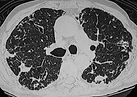

2. Badania radiologiczne (RTG, tomografia)

– cienie guza, zwężenia oskrzeli, przesunięcia, powiększone węzły wnęki i śródpiersia, niedodma.